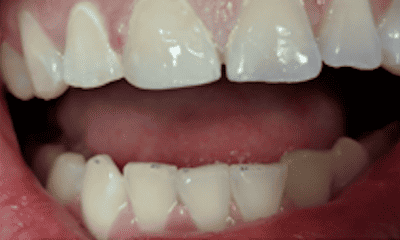

Crowns placed on front teeth to fix worn edges and darkening color of teeth. Crowns created harmony amongst the front teeth and gave the patient a more youthful smile.